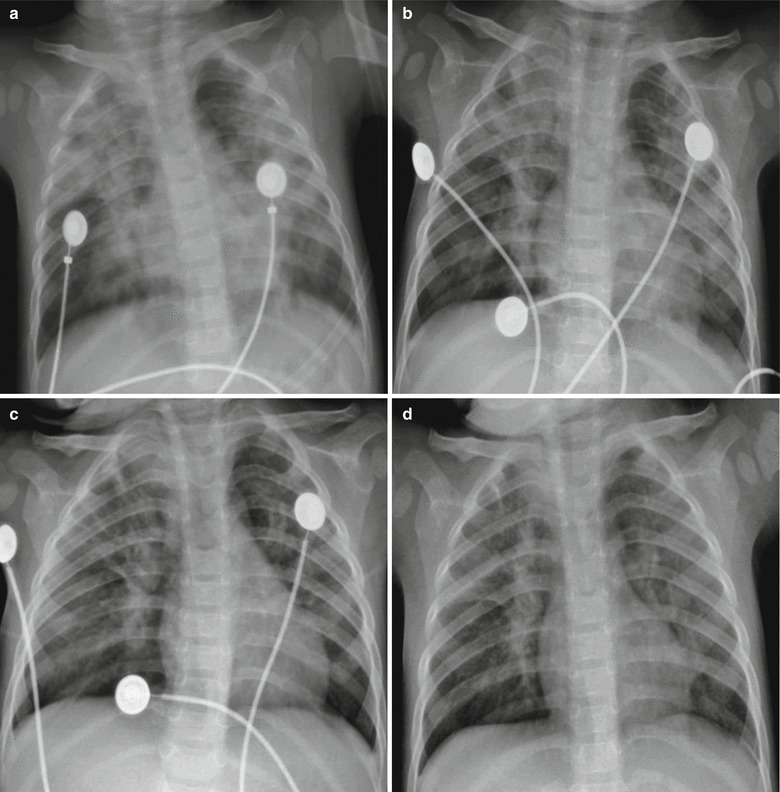

X-ray demonstrates increased, thickened, blurry, and deranged pulmonary markings, which are especially obvious at the middle and medial parts of the both middle and lower lungs. The transparency of lung fields is increased, with pulmonary emphysema as well as enlarged and thickened hilar shadow (Figs. 23.9, 23.10, 23.11, and 23.12). The severe cases are often characterized by flakes of consolidation shadows and extensive exudative lesions in the lungs. The conditions are possibly complicated by pleural effusion and pneumothorax (Figs. 23.13, 23.14, 23.15, 23.16, and 23.17).

Fig. 23.9.

Adult measles pneumonia. X-ray demonstrates flakes of ground-glass opacity with lobular distribution at the posterior segment of right upper lung lobe

Fig. 23.10.

Pediatric measles complicated by pneumonia. X-ray demonstrates enhanced pulmonary markings in the right lower lung

Fig. 23.11.

Pediatric measles complicated by pneumonia. (a) X-ray demonstrates enhanced and blurry pulmonary markings in both lungs and patches of shadows in both lungs, especially in the right lung. (b) By reexamination after the treatment for 4 days, the lesions are demonstrated to be absorbed and improved

Fig. 23.12.

Pediatric measles complicated by pneumonia. (a) X-ray demonstrates enhanced pulmonary markings in both lungs, flakes, and cotton wool-like shadows at the medial part of the right middle and upper lung fields. (b) By reexamination after treatment for 16 days, the lesions at the lungs are demonstrated to be absorbed and improved

Fig. 23.13.

Pediatric measles complicated by pneumonia. X-ray demonstrates multiple flakes of shadows in both lungs with unclearly defined boundaries and unclearly defined left costophrenic angle

Fig. 23.14.

Pediatric measles complicated by pneumonia and pulmonary atelectasis. (a) X-ray demonstrates flakes of shadows in both lung fields along with the pulmonary markings, large flakes of high-density shadows in the right upper lung with clearly defined inferior boundaries, upward shift of the interlobar fissure, and blurry hilar shadows at both lungs. By reexamination after treatment for 2 days, X-ray demonstrates progress of the conditions. (b) X-ray demonstrates enlarged range with lesions in the right lower lung

Fig. 23.15.

Pediatric measles complicated by pneumonia. (a) X-ray demonstrates large flakes of increased density shadows in both lungs with unclearly defined boundaries, and blurry hilar shadow of both lungs. (b) By reexamination after treatment for 2 days, X-ray demonstrates no obvious change of the lesions. (c) By reexamination after treatment for 5 days, X-ray demonstrates enhanced and blurry pulmonary markings of both lungs, multiple patches of shadows in both lungs, and clearly defined hilum. (d) By reexamination after treatment for 9 days, the lesions are demonstrated to be further absorbed and improved

Fig. 23.16.

Pediatric measles complicated by pneumonia. X-ray demonstrates absent pulmonary markings at the lateral part of the right lung field, increased density of the right lung tissues, observable pulmonary compression line, large flakes of consolidation shadows in the left middle and upper lung fields, and gas shadows at the soft tissue of right thoracic wall

Fig. 23.17.

Pediatric measles complicated by pneumonia and acute respiratory distress syndrome. (a) X-ray demonstrates extensive high density in both lung fields and absent pulmonary markings in both lungs. (b) By reexamination after treatment for 1 day, X-ray demonstrates multiple large flakes of shadows in both lungs and increased transparency of both lungs. (c) By reexamination after treatment for 4 days, the lesions are demonstrated to be improved. (d) By reexamination after treatment for 7 days, consolidation density is demonstrated in the lung fields of both lungs with inner bronchial shadows, and poorly defined at both lungs